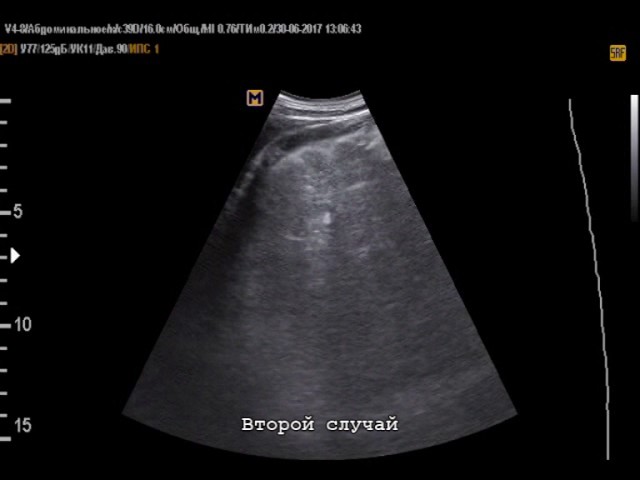

При циррозе врач увидит уплотнение печеночной ткани, так как соединительная ткань плотнее здоровых гепатоцитов. Циррозная печень на снимке будет не серой, а белой. Уплотнение происходит не равномерно, а в виде узлов регенерации. В зависимости от их размера различают мелкоузловую и крупноузловую формы болезни.

На поздних стадиях заболевания формируется асцит — скопление жидкости в брюшной полости. Его хорошо видно с помощью ультразвука даже в небольшом количестве. Заключение о циррозе печени выдается, если на УЗИ обнаружены минимум три признака патологии.

А как выглядит цирроз на УЗИ печени? Его можно предположить при комбинации асцита с изменениями размеров печени, ее эхогенности (плотность ткани, отражающейся на мониторе УЗ-аппарата оттенком серого) и неровным краем, а также с увеличением селезенки, расширением воротной и селезеночной вен. Можно предположить цирроз.